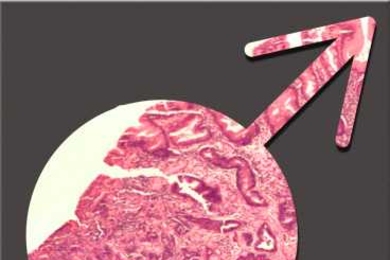

Study explains why men are at higher risk for stomach cancer

MIT researchers show how estrogen protects women from the gastric inflammation that can lead to cancer.